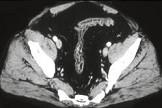

问题 男,41岁,腹痛、腹泻、腹胀、脓血便、里急后重、疲乏无力,结合图像,选择最可诊断 ( )

选项 A、假膜性肠炎 B、结肠淋巴瘤 C、结肠克罗恩病 D、结肠结核 E、溃疡性结肠炎

答案 E